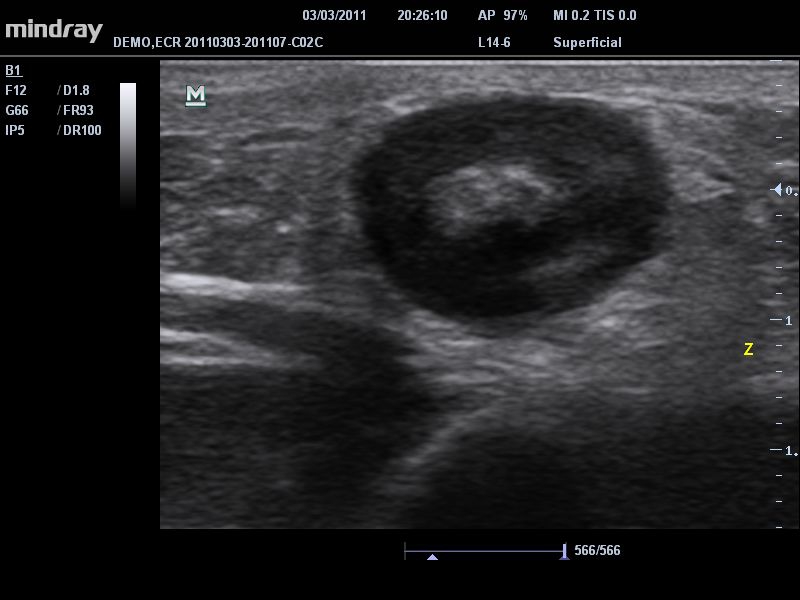

• Высокочастотный линейный датчик 38 мм Mindray l14-6NE